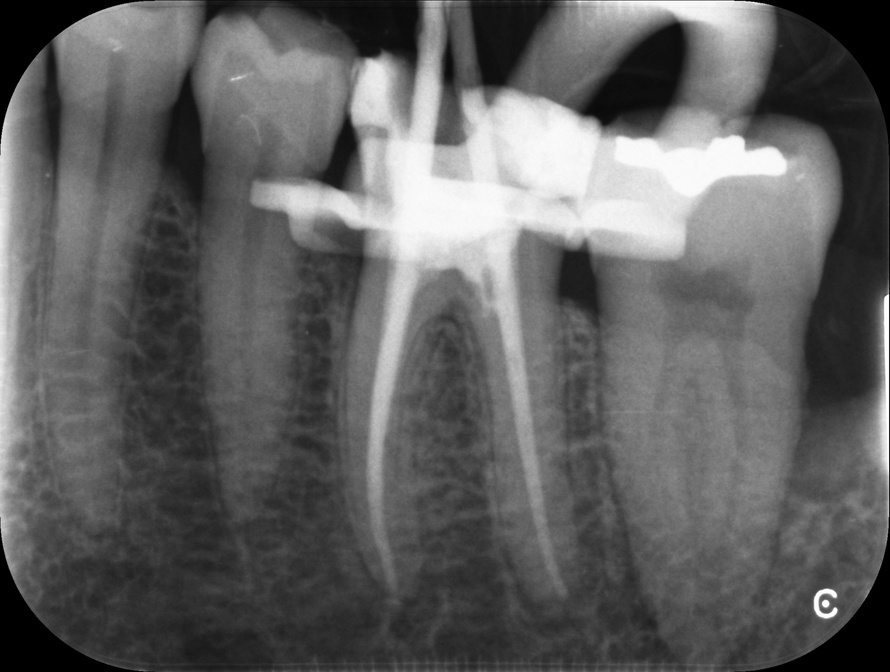

Endodontic Referrals

I am pleased to take endodontic referrals. Curved canals >30 degrees and potentially greater than 50 degrees can be negotiated. Sclerosed canals accessed. Post spaces prepared and the patient returned to you ready to restore.In most cases existing crowns, bridges and veneers can be retained with the endodontic access aesthetically restored after the full canal network has been treated.In the first instance I would prefer a radiograph and a brief list of patient expectations and a tooth history.

There are a number of ways to decide whether you need root canal treatment and the specific x-rays, scans and tests help diagnose your problem.An important sign is the type of pain you have been having with a tooth. It helps me decide if a tooth is in need of treatment and even if it saveable.

I really enjoy undertaking root canal treatments - rising to the challenge and helping people out of dental pain for the long term.I was privileged to be asked to speak at the 2016 BDA Conference, where I have a lecture about providing quality endodontic outcomes to patients, working as a generalist. Avoiding problems and pitfalls and maximising efficiency. One of the main matters that he covered was understanding that what is seen on plane radiography is utterly misleading and should not be the criteria by which a generalist continues treatment once it has been started.

At the 2016 BDA Conference, Thomas spoke about providing quality endodontic outcomes to patients, working as a generalist. Avoiding problems and pitfalls and maximising efficiency. One of the main matters that he covered was understanding that what is seen on plane radiography is utterly misleading and should not be the criteria by which a generalist continues treatment once it has been

started.